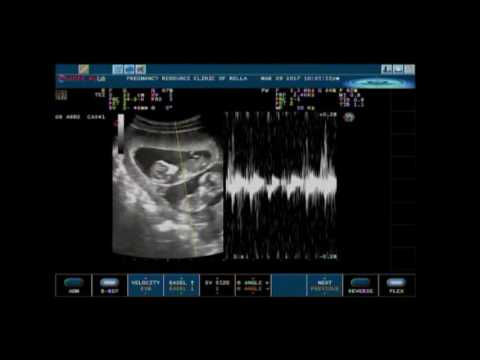

Una ecografía en directo y comentada por el doctor Christopher Baldwin -uno de los médicos que siguieron el embarazo- de los trillizos de Janey Harris.